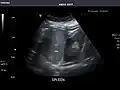

Liver

Ultrasonography of the liver with some standard measurements[6]

In patients with deranged liver function tests, ultrasound may show increased liver size (hepatomegaly), increased reflectiveness (which might, for example, indicate cholestasis), gallbladder or bile duct diseases, or a tumor in the liver.

Ultrasonography of liver tumors involves two stages: detection and characterization. Tumor detection is based on the performance of the method and should include morphometric information (three axes dimensions, volume) and topographic information (number, location specifying liver segment and lobe/lobes). The specification of these data is important for staging liver tumors and prognosis. Tumor characterization is a complex process based on a sum of criteria leading towards tumor nature definition. Often, other diagnostic procedures, especially interventional ones, are no longer necessary. Tumor characterization using the ultrasound method will be based on the following elements: consistency (solid, liquid, mixed), echogenicity, structure appearance (homogeneous or heterogeneous), delineation from adjacent liver parenchyma (capsular, imprecise), elasticity, posterior acoustic enhancement effect, the relation with neighboring organs or structures (displacement, invasion), vasculature (presence and characteristics on Doppler ultrasonography and contrast-enhanced ultrasound (CEUS).